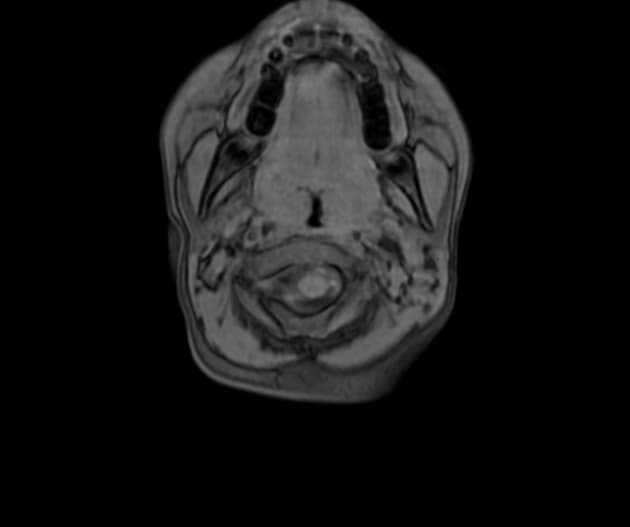

Axial T1

Các dãy xung MRI cho thấy các vùng tăng tín hiệu (hyperintense) ở vỏ não trên hình ảnh FLAIR và T2WI, ảnh hưởng đến các bán cầu tiểu não và vermis tiểu não, không thấy hạn chế khuếch tán trên hình ảnh khuếch tán (DWI/ADC).

Hình ảnh lâm sàng và đặc điểm trên MRI phù hợp nhất với viêm tiểu não cấp tính (acute cerebellitis).

- "Chụp MRI cho thấy tăng tín hiệu trên T2/FLAIR ở vỏ tiểu não, không hạn chế khuếch tán, giúp phân biệt với nhồi máu não."